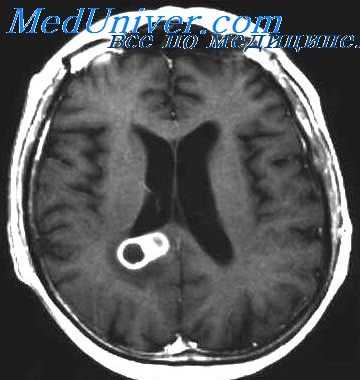

Решающим для подтверждения диагноза менингита является исследование цереброспинальной жидкости. По показаниям проводят дополнительные исследования (рентгенографию черепа и придаточных пазух носа, осмотр глазного дна, электроэнцелографию, эхо-энцефалографию, компьютерную и ядерно-магнитнорезонансную томографию). При люмбальной пункции определяют давление цереброспинальной жидкости, проводят ликвородинамические пробы Стуккея и Квикенштедта, определяют визуальные характеристики жидкости (прозрачность, цвет). В осадке жидкости определяют количество и состав клеток, наличие микрофлоры. Проводят биохимические (количество белка, глюкозы, хлоридов, осадочные пробы и т. д.) и микробиологические исследования.